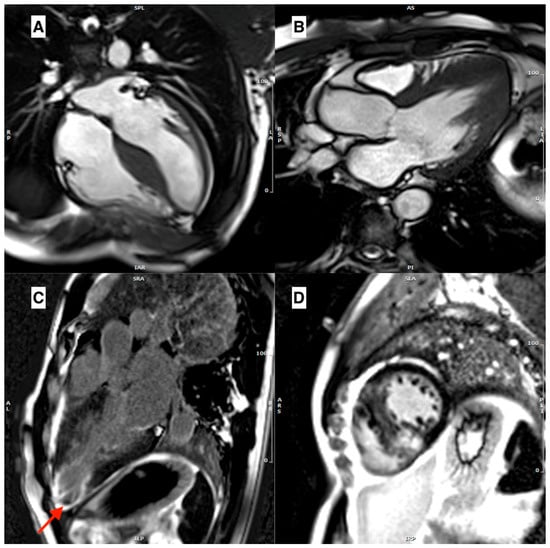

2. HCM Phenocopies (Similarities and Differences)

3. Cardiovascular Magnetic Resonance

3.1. Morpho-Functional Features in Hypertrophic Phenotypes

3.3. Role of Late Gadolinium Enhancement

3.4. Role of Parametric Mapping